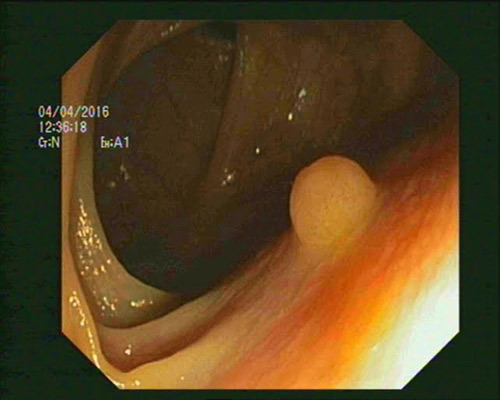

Vì thế chương trình tầm soát ung thư hàng năm của Hiệp hội Ung thư Mỹ khuyến cáo: Ngoài 30 tuổi kể cả nam và nữ, đặc biệt là những người trong gia đình có tiền sử ung thư đại trực tràng, cứ 5 năm nên nội soi đại tràng/ lần. Trong nội soi phát hiện polyp đại tràng thì cần cắt bỏ để phòng ngừa ung thư”.

Trong nội soi phát hiện polyp đại tràng, bác sĩ sẽ cắt bỏ để phòng ngừa ung thư. |

Một trong những phương pháp sàng lọc, phát hiện sớm hiệu quả là nội soi đại tràng. Có thể lựa chọn một trong 2 hình thức: Nội soi không gây mê hoặc có gây mê. May mắn kết quả nội soi hoàn toàn bình thường, không có tiền sử gia đình, bạn có thể duy trì nội soi định kỳ 5 năm/lần. Khi quá trình soi phát hiện tổn thương nghi ngờ, thời gian cần nội soi lại sẽ rút ngắn tùy theo tình trạng tổn thương thực tế của bạn, bác sĩ chuyên khoa sẽ lên kế hoạch theo dõi cho bạn.